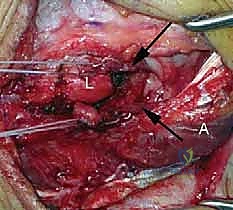

* اختبار الانزلاق الدوراني (Lateral Pivot-Shift Test of the Elbow): وهو الفحص الأهم. ينام المريض على ظهره، ويقوم الدكتور برفع الذراع فوق الرأس، ثم يطبق قوة أروح (Valgus) مع استلقاء الساعد وضغط محوري بينما يقوم بثني الكوع. إذا كان الرباط ممزقاً، سينخلع رأس الكعبرة جزئياً، وعند الوصول إلى زاوية ثني معينة (حوالي 40 درجة)، يعود رأس الكعبرة لمكانه مع صوت "طقطقة" (Clunk) مسموع ومحسوس.